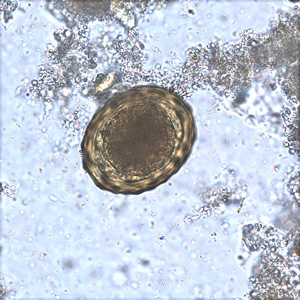

Acanthamoeba cysts

two layered wall with pores